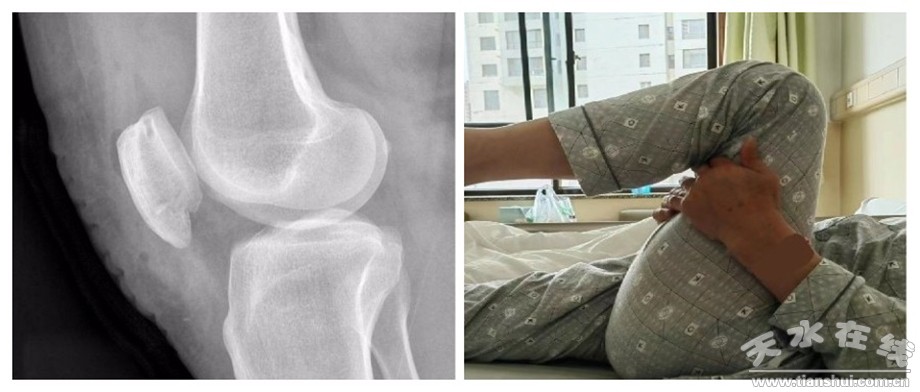

考虑到患者高龄,其必然存在不同程度的骨质疏松,而且,此次外伤导致的髌骨下极骨折粉碎程度重,经过对患者影像学资料全面评估后,市一院运医团队巧妙应用运动医学治疗理念,为该患者实施了以“柔”代“钢”的微创、弹性固定术。手术取膝前短切口(约4cm),术程注重骨折周围软组织的保护,术中采用聚乙烯高强线依次完成“折端聚拢”、“高位吊索”关键步骤,完美恢复了骨折端的解剖对位,固定强度可允许患者术后90°范围即刻屈膝。

以“柔”代“钢”的微创、弹性固定技术,能够恢复髌骨下极骨折的解剖对位,同时也能满足早期功能锻炼的负荷要求。相较传统的手术方式,该项新技术杜绝了“钢”性内固定带来的诸多并发症,同时,因其特有的无“痕”固定,无需二次行内固定取出,从根本上节省了患者的治疗费用,减少了患者的手术疼痛,改善了患者的就诊体验,提升了患者的就医获得感。